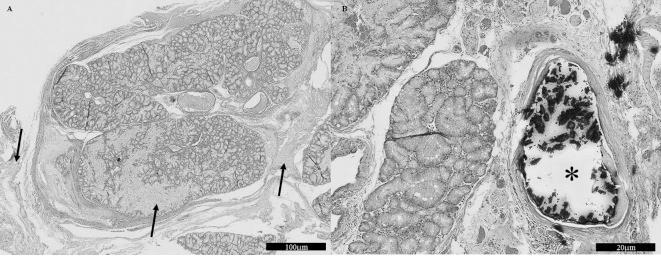

A 10-year-old castrated Shih-Tzu male dog was referred for examination of acute right exophthalmos, protrusion of the third eyelid and soft tissue swelling ventral to the globe. Ultrasonography revealed echogenic fluid around the right globe. Computed tomography (CT) showed an enlarged right zygomatic salivary gland compared with the left zygomatic gland and an amorphous cystic mass ventral to the right globe. Hyperdense material, which we suspected to be a sialolith, was identified in the right zygomatic gland. The zygomatic gland and the cystic lesion were removed, and a zygomatic sialocele with sialolith and ductal obstruction were found by histopathological examination. CT was a useful diagnostic tool for zygomatic sialolithiasis.

一只10岁已去势的雄性西施犬因急性右眼球突出、第三眼睑突出和眼球腹侧软组织肿胀前来就诊。超声检查显示右眼周围有回声增强的液体。计算机断层扫描(CT)显示右侧颧唾液腺比左侧颧腺肿大,且在右眼球腹侧有一个无定形囊性肿块。在右侧颧腺中发现了高密度物质,我们怀疑其为涎石。切除了颧腺和囊性病变,组织病理学检查发现了伴有涎石和导管阻塞的颧唾液囊肿。CT是诊断颧涎石病的一种有用的诊断工具。